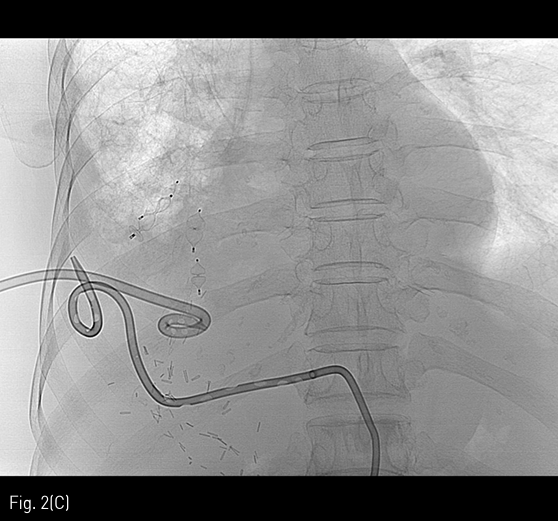

Fig 2C

Image obtained after completion of bronchus embolization (C).